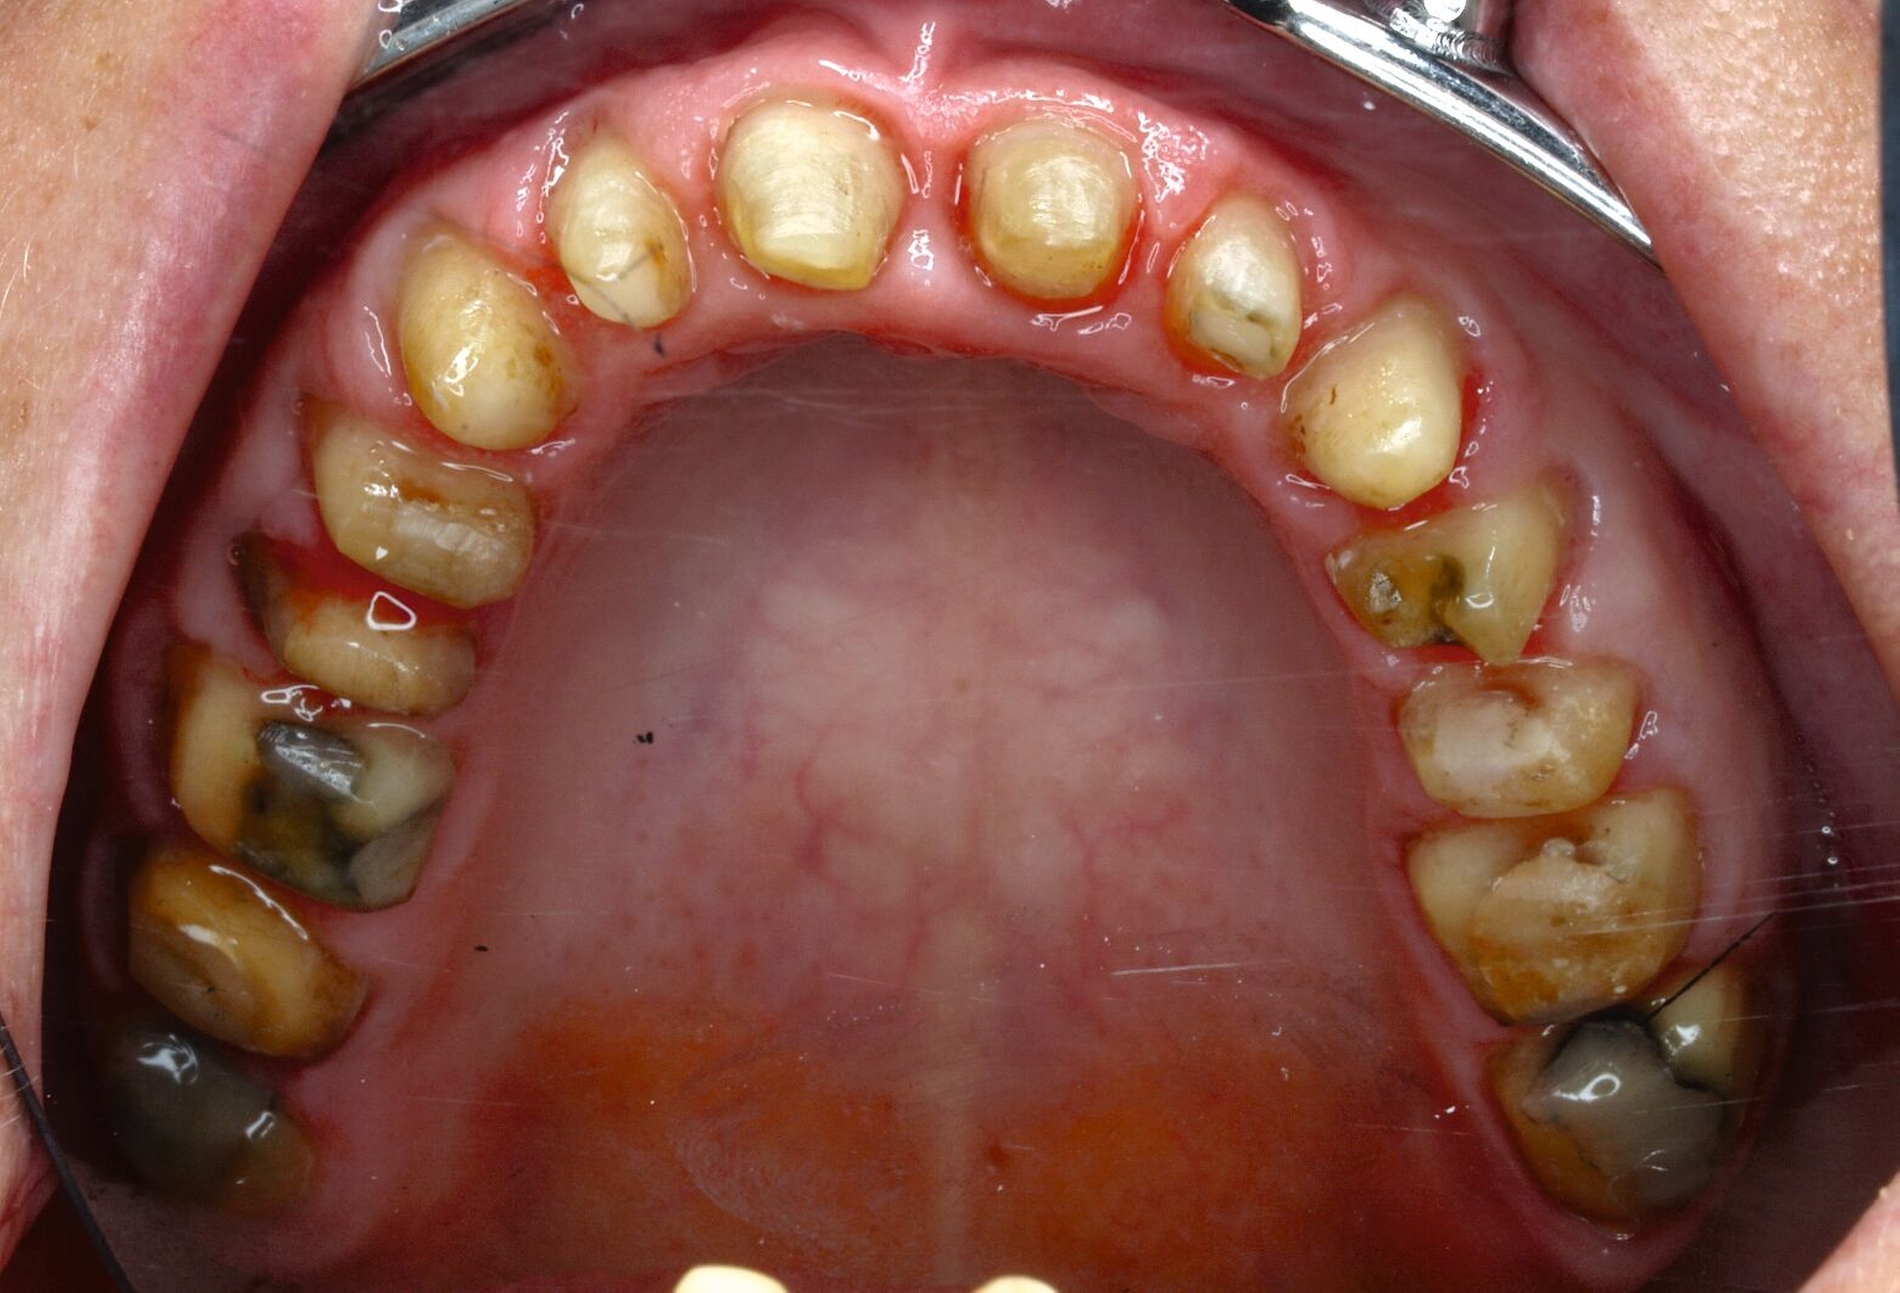

Klinisch zeigten sich diverse großflächig, mehrheitlich mit Amalgam gefüllte Seitenzähne, suffiziente endodontische Behandlungen an den Zähnen 16 und 14 sowie intakte Kronen an den Zähnen 16 und 48 (Abbildung 2). Ein Parodontaler Screening-Index (PSI) wurde erhoben (1-1-0-0-2-1), der stabile Verhältnisse nachwies. Das funktionelle CMD-Screening zeigte eine nicht-druckdolente Kaumuskulatur sowie eine uneingeschränkte Mundöffnung ohne Reiben und Knacken.

Tabelle 1 zeigt das entsprechende Befundschema mit den Taschentiefen mesial und distal, den Lockerungsgraden und den Sensibilitätsüberprüfungen mittels Kältespray (ViPr). Die Ruheschwebelage wurde mithilfe des Zielinsky-Zirkels auf 2 mm bestimmt. Die Nonokklusion im Seitenzahnbereich konnte auf circa 1,5 mm bemessen werden. Tabelle 2 spiegelt das entsprechende Okklusionsprotokoll wider. Das Okklusionsprofil wird auch in den Abbildungen 3a bis 3c deutlich.